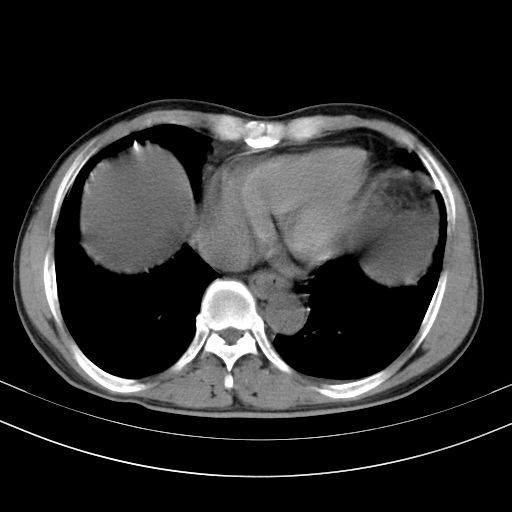

以下是引用随光逐影在2010-2-28 10:23:00的发言:[br]1)考虑肝癌;建议行ct增强扫描检查。2)肝硬化,脾大,腹水。3)慢性胆囊炎。

以下是引用dyqct在2010-2-28 16:44:00的发言:[br][quote]以下是引用随光逐影在2010-2-28 10:23:00的发言:[br]1)考虑肝癌;建议行ct增强扫描检查。2)肝硬化,脾大,腹水。3)慢性胆囊炎。